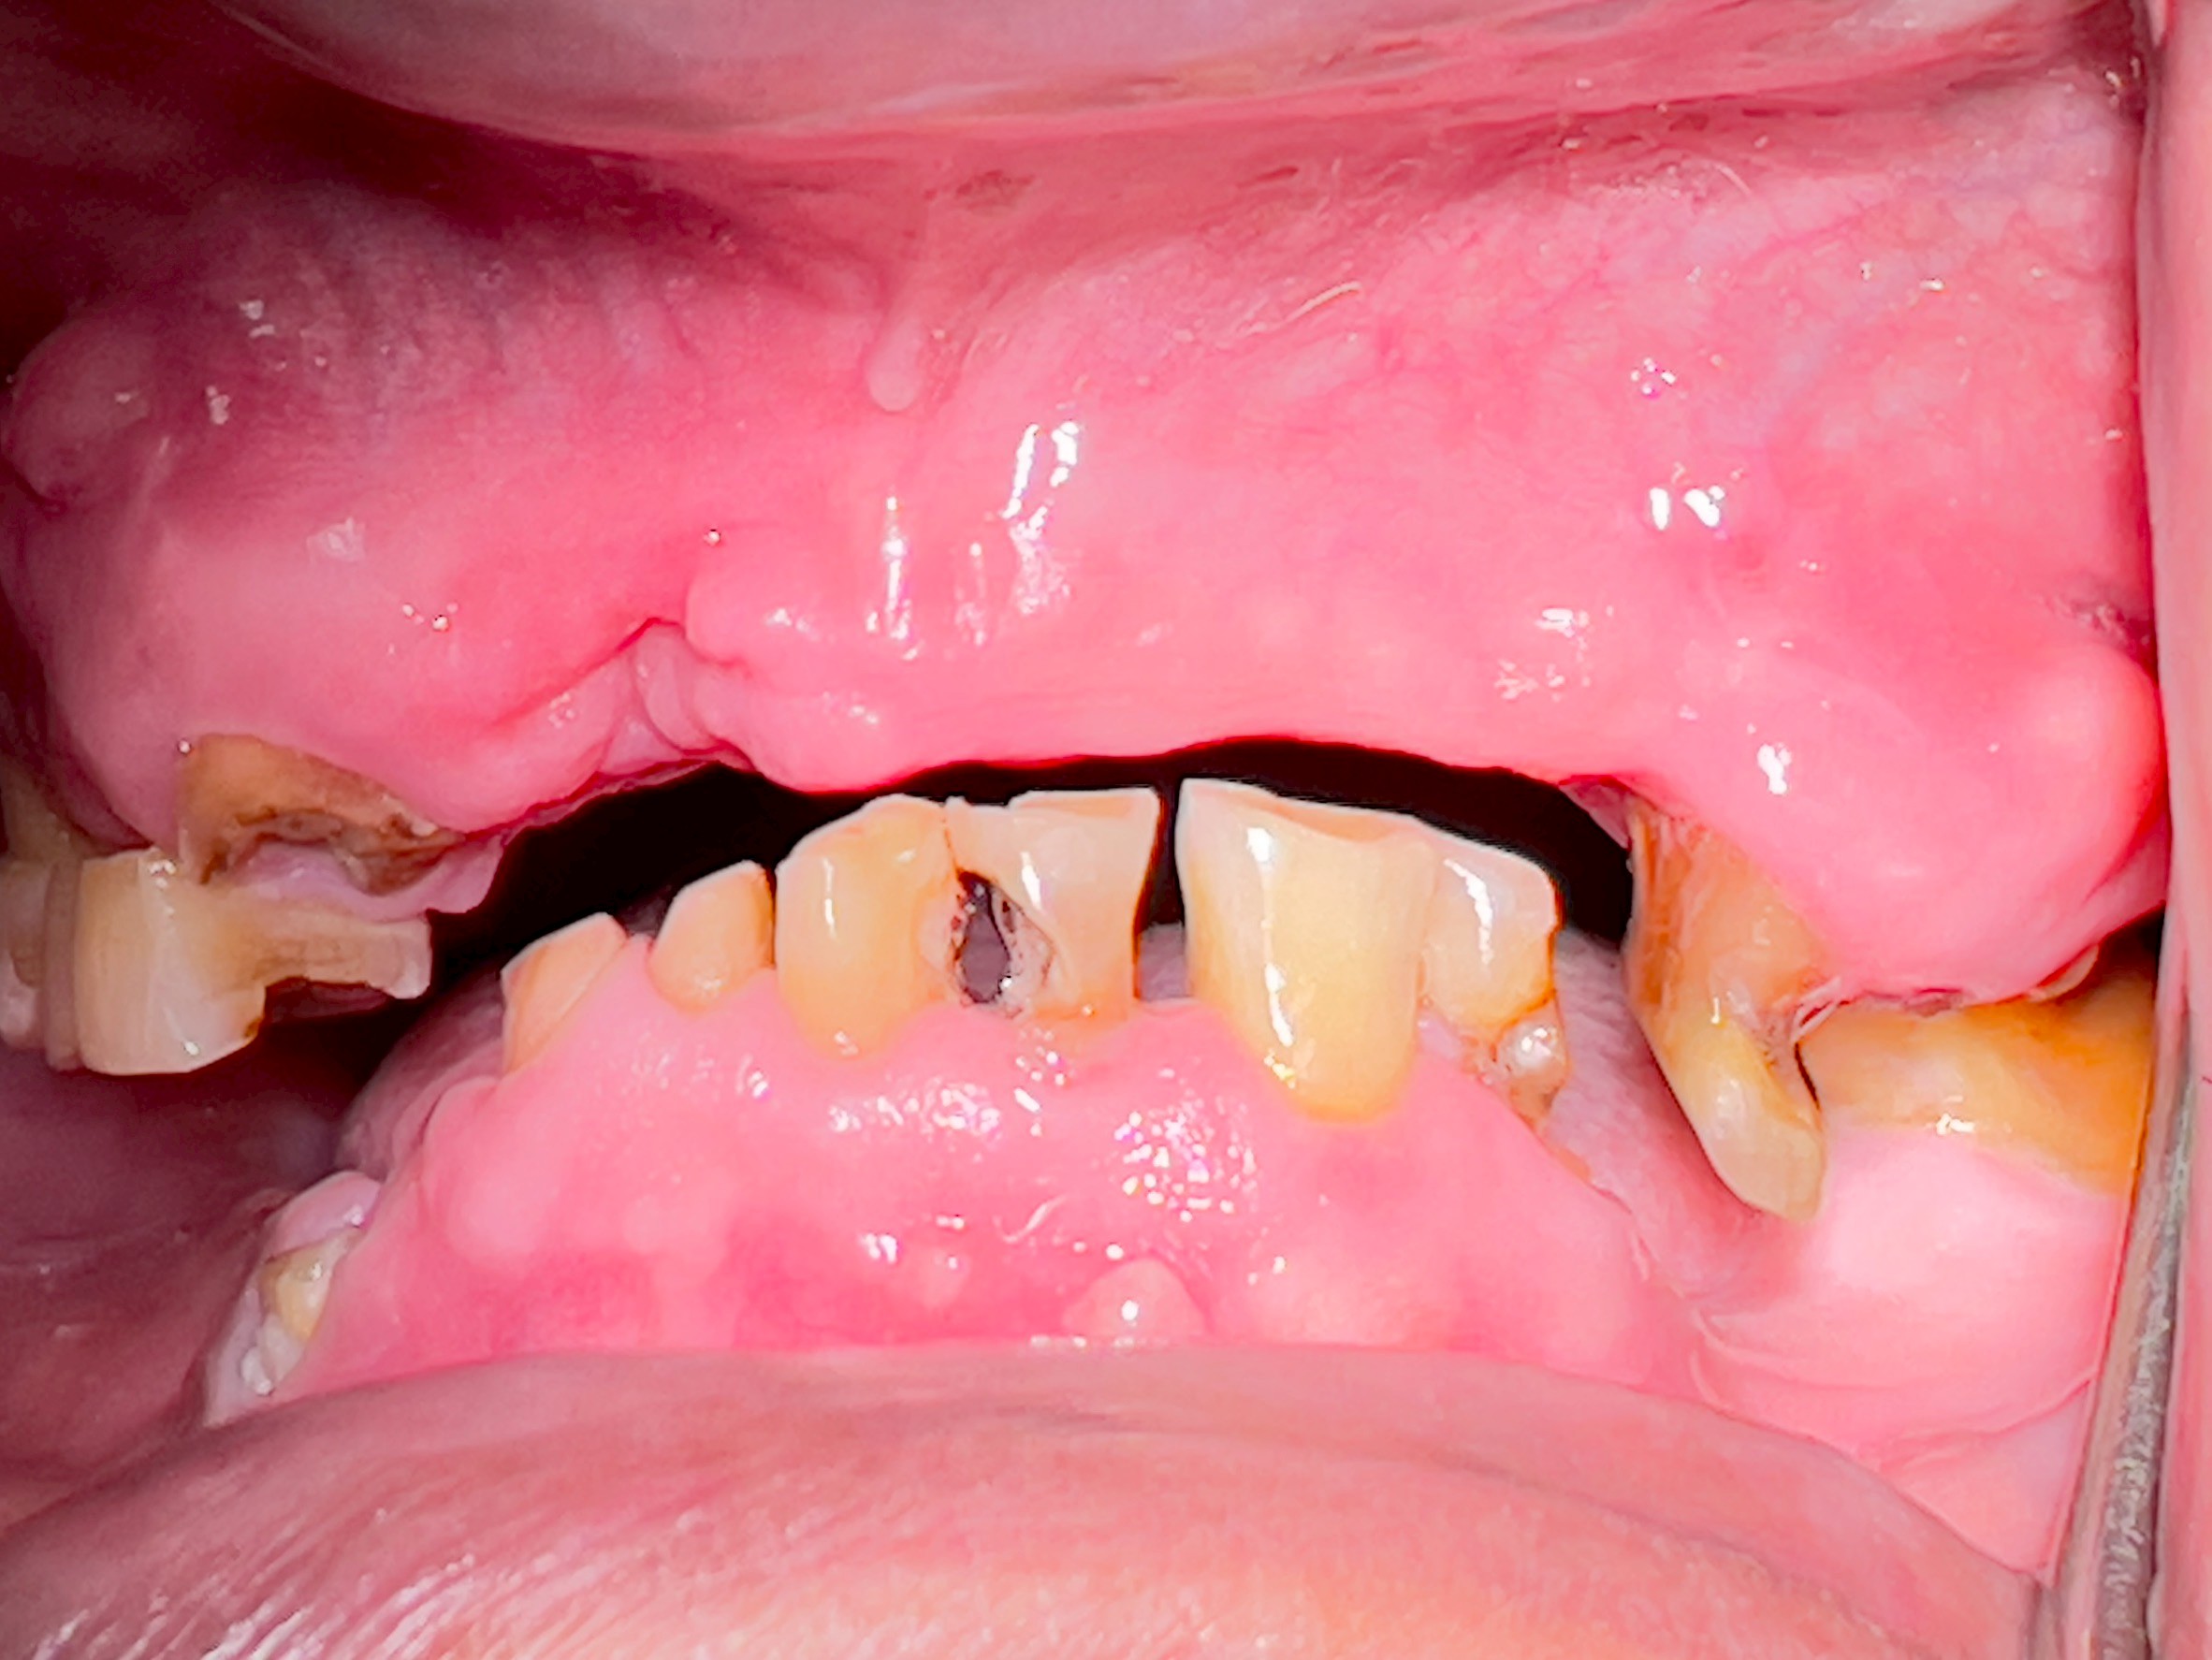

All-on-4 Implants Lower Jaw + Partial Denture Upper Jaw